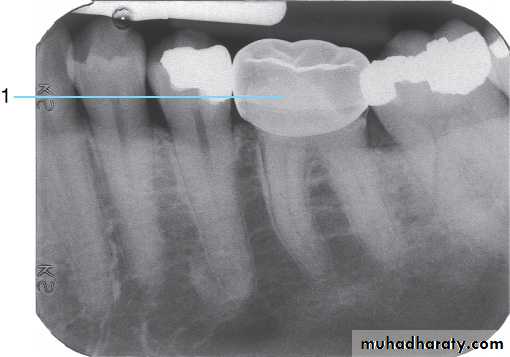

Teeth are composed of pulp (arrow on the secondmolar), enamel (arrow on the first molar), dentin (arrow onthe second premolar), and cementum (usually not visibleradiographically).